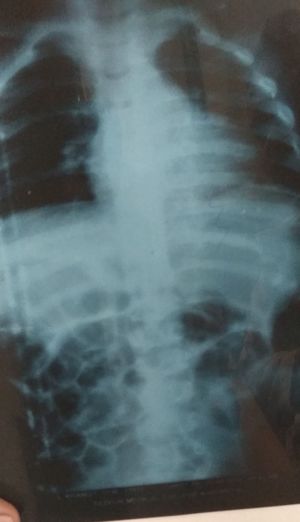

Hirschsprung's Disease

X-ray of Hirschsprung Disease

I could never tell HSD from this X-Ray image, least i could is maybe small bowel obstruction (SBO) pattern , try reposting this with a better angle of the scan, can anybody see Anything significant on this image?